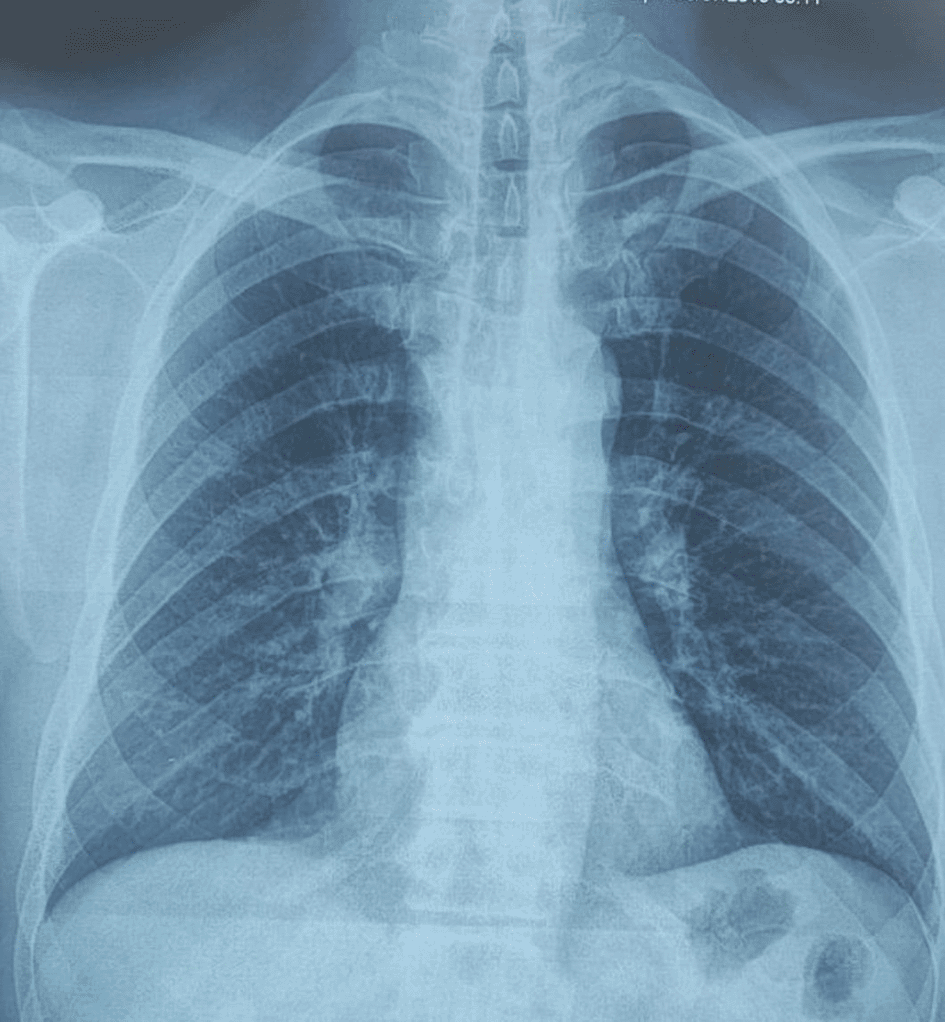

A 58-year-old male with a continued 70-pack-year smoking history was referred to our department for the endoscopic treatment of an endotracheal tumor. Four years previously, the patient presented with isolated shortness of breath and was treated for chronic obstructive pulmonary disease (COPD). Physical examination showed wheezes, and spirometry had met the GOLD criteria for the diagnosis of COPD with very severe airflow limitation (post-bronchodilator FEV1: 1.02 L (29%), post-bronchodilator FEV1/FVC ratio: 45%). The patient was subsequently hospitalized for bilateral hypoxemic pneumonitis and acute respiratory failure, which was treated as COPD exacerbation with a good evolution under usual treatment. On admission in our department, his clinical examination was normal, and his oxygen saturation was 97% (room air). Laboratory tests and chest radiography revealed no abnormalities (Figure 1). Chest computed tomography (CT) scan showed a hypodense pedunculated budding lesion of the left anterolateral tracheal wall located just above the carina, 12 cm from the vocal cords and measuring 17 × 15 × 10 mm (Figure 2). Flexible bronchoscopy confirmed an endotracheal lesion, but biopsies were non-contributory. Based on these findings, laser-assisted mechanical resection of the tumor has been validated as a feasible treatment option. Rigid bronchoscopy, performed under general anesthesia, revealed a non-vascularized pale pink tumor located at the lower third of the trachea approximately 1 cm distal to the carina, which obstructed 60% of the tracheal lumen (Figure 3A). Following the initial exploration, the tumor was removed at the tip of the bronchoscope following laser treatment (15W,364 J). No other instrument was used. On the final examination, a small tumor residue was observed (Figure 3B). There were no complications, and the patient was rapidly discharged. The tumor measured 18 × 10 mm (Figure 4). Histopathological examination of the samples stained with Hematoxylin and Eosin (H&E) showed the presence of hypertrophic seromucous gland admixed with variable amounts of fibrous adipose tissue, spindle cells, and myxoid stroma (Figure 5). The diagnosis of endobronchial HC was established. The patient subsequently underwent follow-up flexible bronchoscopies, which all revealed that the tumor residue was stable and did not obstruct the tracheal lumen with a follow-up of three years (Figure 6). The patient is currently asymptomatic, and his last spirometry examination revealed no abnormalities.